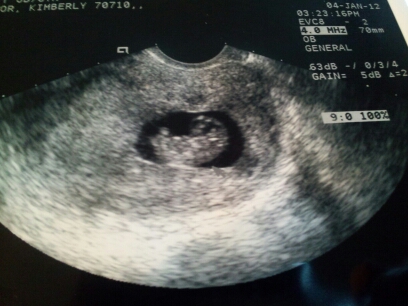

I’m to be an uncle again.

January 6, 2012